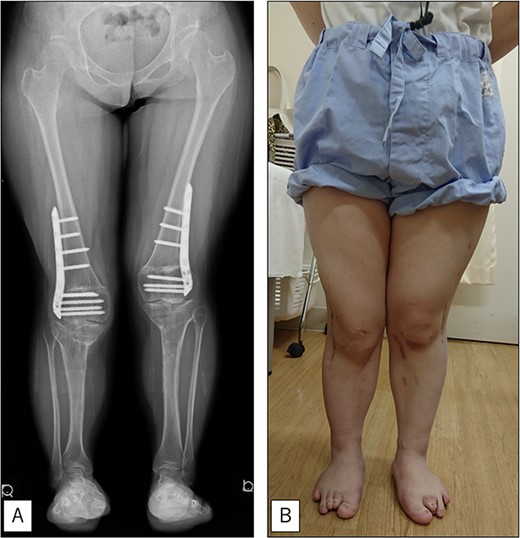

A 23-year-old woman presented with bilateral knee pain and gait abnormalities owing to marked lower extremity deformity. She was diagnosed with EVC as a child but had never been followed up by orthopedics because she was not in pain. On physical examination, marked valgus instability was observed in both knees, and the motion of both knees ranged from 10° to 135°. Radiographic examinations of both knees, including computed tomography, showed valgus deformity, lateral and anterior depression of the proximal lateral tibial plateau, and external rotation deformity of the lower leg. Patellar dislocation was observed in the right knee (Fig. 1). The radiological angles are presented in Table 1. The right knee underwent surgery first, followed by the left 10 months later. Lateral and medial skin incisions were made. Extensive lateral retinacular release, fractional lengthening of the distal lateral hamstring, and Z-lengthening of the iliotibial band were then performed. At this stage, peroneal nerve strain was identified, and decompression of the peroneal nerve was performed. Osteotomy was subsequently performed on the tibia. Closed-wedge varus and derotational osteotomy of the proximal tibia and open-wedge varus osteotomy of the distal femoral varus were performed. In addition, vastus medialis advancement was performed on the right knee, and patellar realignment was achieved in extension (Fig. 2). However, the knee showed a subluxation tendency owing to flexion of >30°; therefore, the postoperative rehabilitation plan progressed more slowly than that of the left knee. Range of motion training began on the left knee immediately after surgery without any restrictions, but on the right knee only after 3 weeks of postoperative immobilization in the extended position. However, ambulation exercise was performed on both knees with no loading for 3 weeks, then partial loading was initiated, and full loading was permitted at 8 weeks postoperatively. Early postoperative standing radiography showed residual mild valgus deformity of the lower limbs (Fig. 2, Table 2). In addition, the right knee showed patellar re-dislocation 2 months postoperatively, and the patellar deformity gradually progressed owing to the femoral implant; therefore, the patient underwent implant removal, tibial tubercle transfer, and medial patellofemoral ligament reconstruction 1.5 years after the initial surgery (Fig. 3). Six months later, she fell while walking and developed a fracture at the osteotomy of the right femur; open reduction and internal fixation were performed (Fig. 4). The remaining years passed uneventfully, and 10 years after the initial surgery, the patient still had mild valgus deformity of the lower limbs, but had no recurrence other than that experienced immediately after surgery, no complaints of knee pain, and a stable gait (Fig. 5, Table 2).

At the final follow-up 10 years after the initial surgery. (A) Standing anteroposterior view. Although mild valgus deformity of the lower limbs remained, no recurrence occurred except for that experienced immediately after surgery. (B) Photograph of the entire lower legs.

In the current patient, mild valgus deformity of the lower limbs persisted immediately after surgery, and there was no repair of the lateral plateau; however, the deformity had not recurred 10 years after surgery. One possible reason for the lack of recurrence is that the patient was an adult and the closure of the growth plate had been recognized preoperatively.